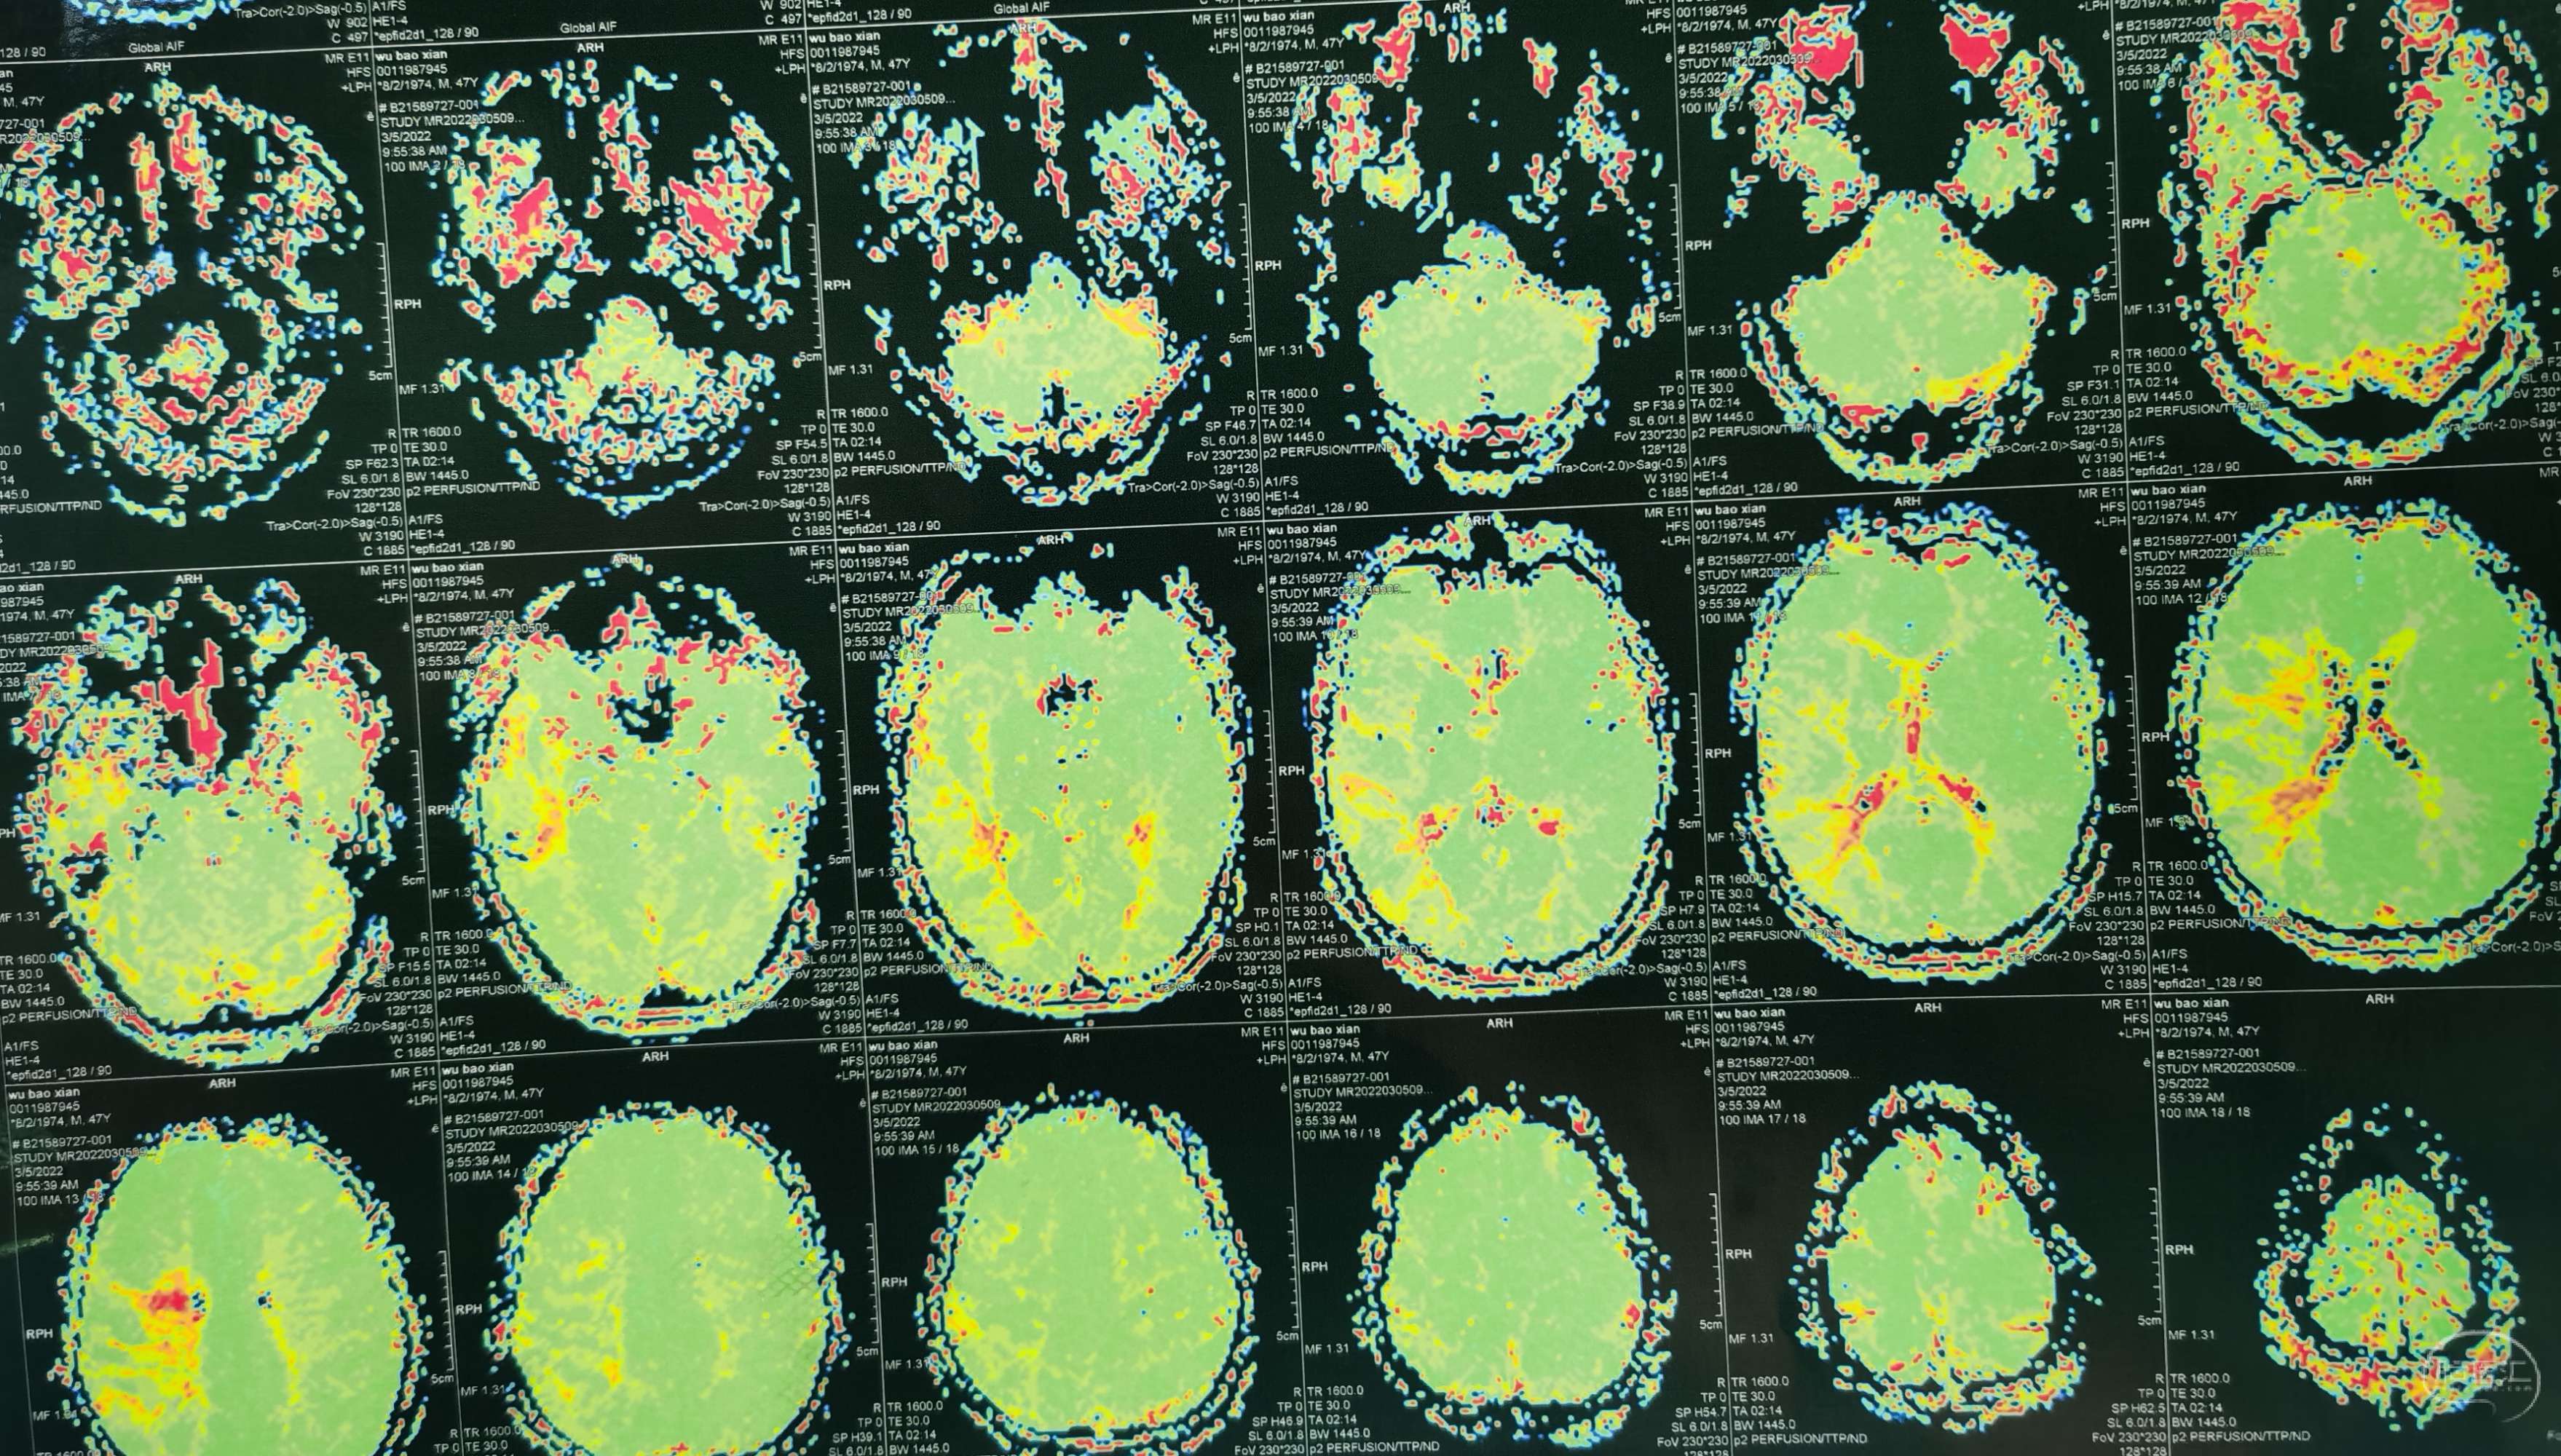

脑灌注提示:左侧大脑半球低灌注缺血。

脑灌注提示:右侧大脑半球低灌注缺血。

脑灌注提示:双侧大脑半球低灌注缺血。

脑灌注提示:双侧大脑半球低灌注缺血。

脑灌注提示:双侧大脑半球低灌注缺血。